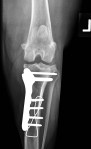

Crâniocaudale